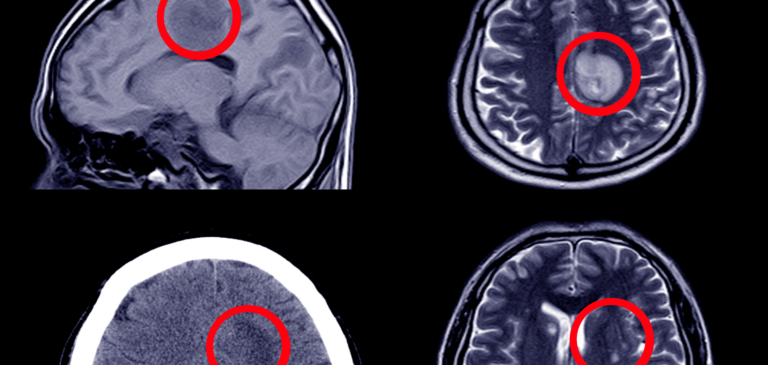

Misdiagnosis of Strokes, Mini-Strokes, and Aneurysms

The American Stroke Association reports strokes are the third leading cause of death and a leading cause of disability. But what if you are misdiagnosed?